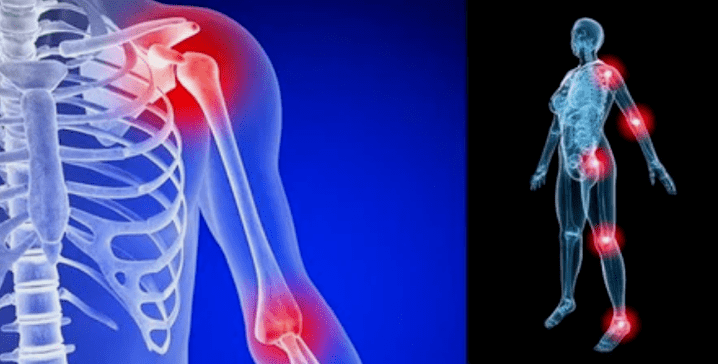

- Schwellung mat Rötung. Et gëtt lokal no bei der kranker Gelenk lokaliséiert, dëst beweist en entzündleche Prozess an d'Progressioun vun der Krankheet. Den Dokter versteet datt déi synovial Shell betraff ass, dëst provozanzt d'Akkumulatioun vu Flëssegkeet a verstäerkte Péng;

limb Deformatiounen. Erschéngt an enger vernoléisseger Form vun der Krankheet, beweist déi komplett Zerstéierung vum Knorpel an der Erscheinung vun Osteophyten. An dësem Graf ass dann op eng Glidderen op enger Erhéijung vun där Krounung betrëfft, déi de ganze Glibbum beaflosse kann.

Méiglech Komplikatiounen:

- De Gelenk ass komplett zerstéiert;

- De Glibband ass üblech, all Bewegunge ginn extrem schwéier;

- Behënnerung;

- Staark Deformatioun vum Gelenk oder der ganzer Glied.